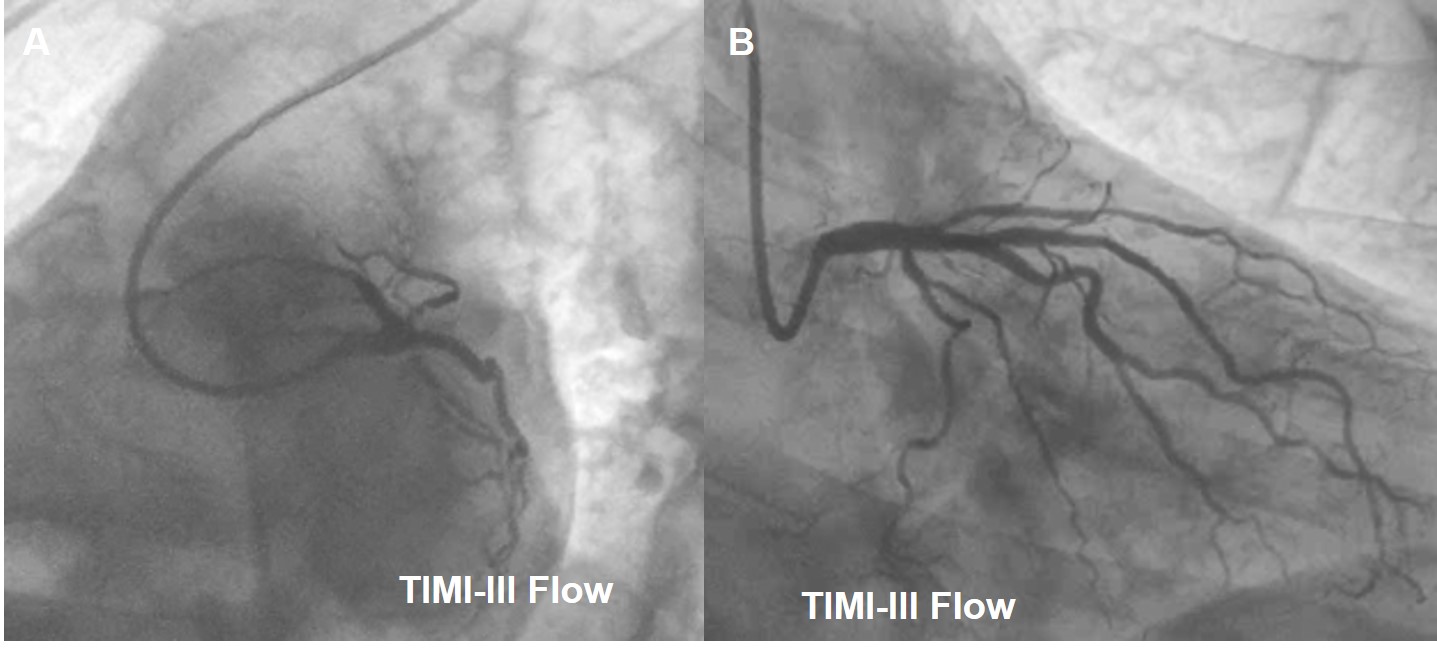

Coronary angiogramrevealed double vessel disease with D1 Osteal 90% Stenosis, Ramus-osteoproximal 90% Stenosis.

Procedure performedthrough right radial artery LMCA engaged with 6Fr EBU 3.5 Guiding catheter, 0.014X180cmRun-through wire placed in LAD and another Run-through wire was placed in Ramus.Predilatation done with 2.0x12mm Balloon. RAMUS stenting was done with 2.75X18mm Onyx DES. Diagonaldilatation done with 2.0 x 25mm PREVIL Drug Eluting Balloon. Thefinal result was good with TIMI III Flow without any edge dissection andresidual stenosis. Patient was discharged in a stable status on 3rd postprocedure day without any CV Symptoms.